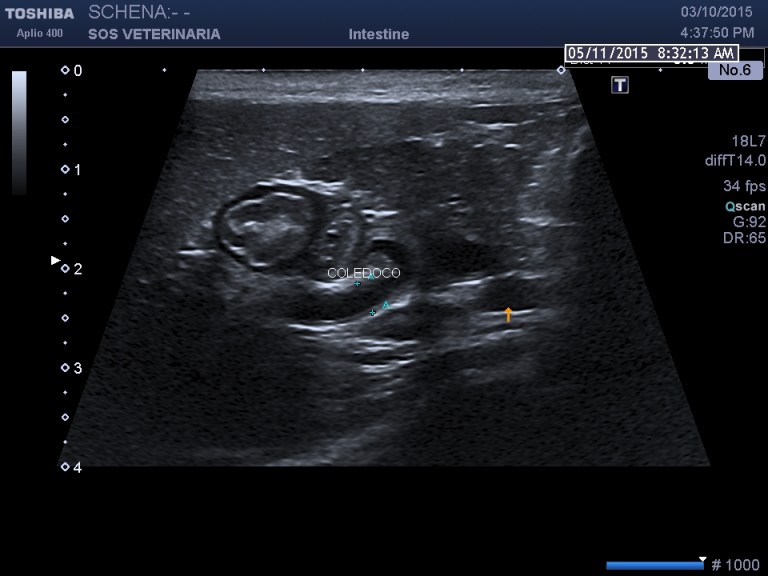

PROCESSO INFIAMMATORIO COLEDOCO E COLECISTE FORMAZIONE DI UN DIVERTICOLO ED ECTASIA DOTTO PANCREATICO

Gatta comune europea vive fuori e dentro casa pportata alla visita per anoressia e depressione rilevato ittero clinico

evidente la dilatazione e l’ispessimento   della parete  a carico di coleciste e coledoco con   formazione presfinterica di un ampolla ectasica simil diverticolo probabilemente secondaria alla cronicita’ del processo ,non si evidenziano ostacoli calcolotici o neoformazioni occludenti  il deflusso intra o extraluminali e a livello della papilla , il pancreas si presenta omogeneo ipoecogeno iperplastico trama vasale  ben evidenziabile .

Una  terapia di lunga durata con prednisolone alla dose di 0,5 mg/Kg sid comninata con marbofloxacillina e metronidazolo ha portato  dopo 4 settimane a risoluzione clinica e di laboratorio e ad un notevole miglioramento dell’imaging ,permane a distanza di 2 mesi  l’ectasia del dotto pancreatico e mofificazioni preampollari del coledoco con grado di distensione molto ridotto. Si e’ concluso  per un processo infiammatorio  possibile complesso colagioepatie ibd pancreatite (triatide)  con fenomeni iperplastici e fibrotici  a livello della papilla duodenale  e stenosi parziale del deflusso intraparietale duodenale ,tuttavia l’assenza di esami istopatologici non permette conclusioni certe eziopatogenetiche se non le evidenze riscontrate durante il decorso. Dopo due mesi il paziente alla sospensione dei farmaci mantiene la remissione.